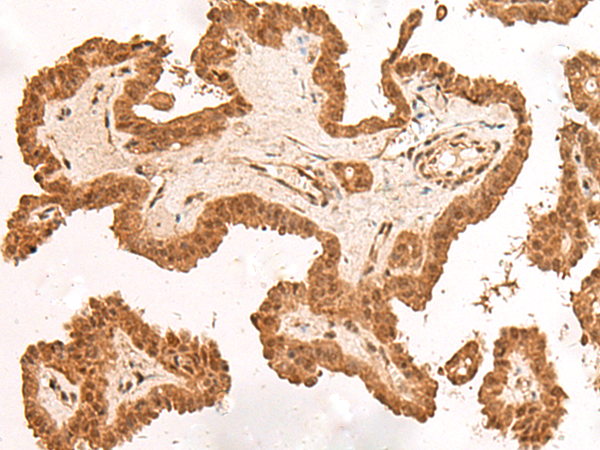

IHC positive control: |

Human esophagus cancer and Human thyroid cancer |